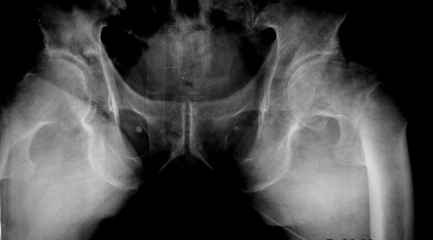

Это стабильный перелом А1.2. Противопоказано - остеосинтез винтами (не достаёт стабильности при переломах типа А), эндопротезирование - неоправданно травматичное вмешательство.

Показан - или DHS, или гвоздь. В случае стабильных переломов, таких как данный, биомеханически это работает одинаково хорошо. То есть, если пожилой пациент не может ходить при помощи костылей - полная нагрузка не противопоказана, даже в случае остеосинтеза DHS. Преимущество DHS - меньшая цена. Преимущество гвоздей - миниинвазивность. Но, ещё раз подчеркну, биомеханически при переломах А1 - это одно и тоже. При нестабильных переломах- А2 и А3 - показан гвоздь. А если DHS - то только с накладкой. Эндопртезирование при переломах типа А проводится чрезвычайно редко - только при данных переломах на фоне ДОА. И то не всегда и не всеми ортопедами это поддерживается. Так что выдумывать не надо - следуйте общепринятому протоколу.